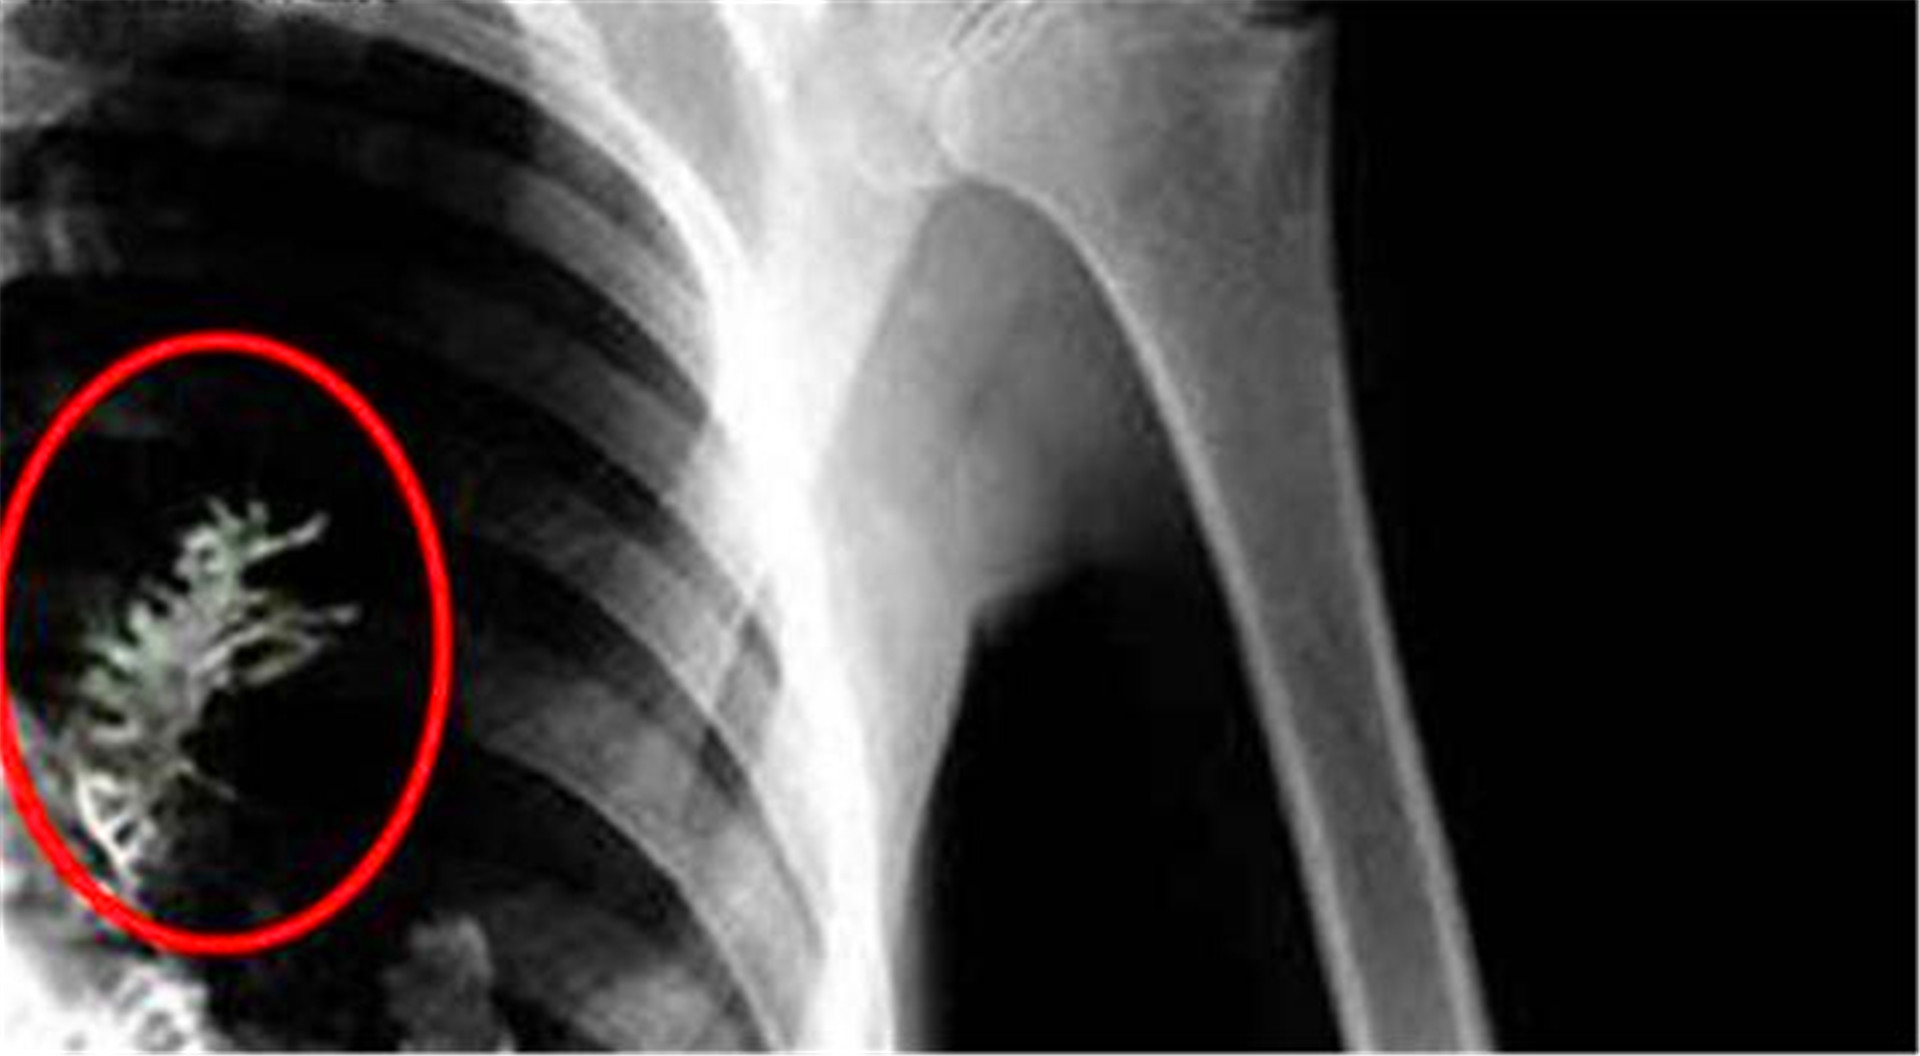

西多尔金决定接受手术,即便手术也不能保证痊愈还可能发生意外,但西多尔金为了自己的家人决定试一下。西多尔金决定瞒着自己的家人,自己在医院动手术。 当西多尔金真的做起手术时,医生们打开他的胸腔,发现里面并没有肿瘤,医生在他肺里找到了一棵冷杉树。这让在场的医护人员吓了一跳,竟然在病人的身体里长出一颗冷杉树。

医生明白过来,在西多尔金的身体里并不是肿瘤,而是一颗冷杉树。这棵小树苗让医生误诊,让西多尔金这位俄罗斯男子被确诊为肺癌。最后将冷杉树在西多尔金的身体里取出,西多尔金也成功的活了下来。 医生十分好奇,西多尔金的身体里怎么会有一颗冷杉树呢?

在西多尔金多次回忆后,得知:十几年前,西多尔金好妻子在花园里散步,后来突然刮起了大风。在风里,西多尔金感觉有一个东西进了他的鼻子,自己打了好几个喷嚏,也没有将东西弄出来。在第二天醒来后,西多尔金发现鼻子里的东西没了,也就没有在意这件事情。 现在后想起来,那进入鼻子里的东西应该是冷杉树的种子,顺着他的呼吸道进入肺部。在经过这么多年的时间,竟在他的肺部生根发芽,甚至长出了树叶。